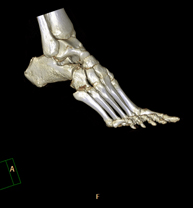

- Ankle-toe CT

Radiological examination based on an X-ray system and detectors that rotate around the patient, reconstructing the images by computer (multidetector computed tomography - MDCT) to study the bones, muscles and joints of the ankle and foot.